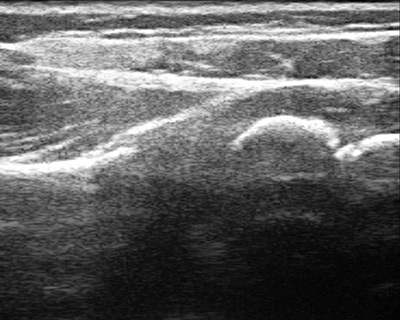

Figure 3b: Normal shoulder ultrasound

Many patients come to us too late to implement the teapot splint, and shoulder tightness with internal rotation has already set in. In children less than a year of age, it may be possible to stretch out the shoulder using botulinum toxin to temporarily weaken the muscles that turn the shoulder in, and then to cast the shoulder in a position of external rotation (Figure 4). This has to be done with the child asleep and so requires general anesthesia. Ultrasound is used to confirm that the joint is in place after the shoulder is stretched, and is it also used intermittently after the cast is removed to make sure that the shoulder is growing and developing well. A teapot splint may be used after casting for up to two years during sleep to maintain the shoulder position.